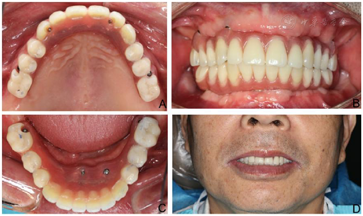

(3)术后1周,制取上颌种植基台水平印模及下颌无牙颌印模,制作蜡堤记录上下颌颌位关系,采用息止颌位法确定垂直距离,吞咽咬合法确定水平关系,转移颌位关系后,当日制作上颌种植体支持式固定义齿及下颌可摘总义齿过渡修复(图6)。上颌修复至第二前磨牙,下颌修复至第一磨牙,调整咬合接触,戴牙后2周、1个月复诊,下颌义齿组织面重衬、调牙合后义齿稳定。

(4)下颌拔牙后4个月(2016年1月)复诊,口腔CBCT检查43、44区骨组织早期愈合(图7),牙槽嵴顶黏膜愈合良好(图8A),口腔局部阿替卡因肾上腺素注射液浸润麻醉,32、42区轴向植入Nobel Speedy4 mm×13 mm种植体,35区斜行植入Nobel Speedy4 mm×15 mm种植体,43、44区骨组织愈合不良,清理肉芽组织后呈凹坑型骨缺损(图8B),45区倾斜备洞穿越44、43骨缺损区植入Nobel Speedy4 mm×18 mm种植体(图8C),4颗种植体初期稳定性均达到35 N·cm,安装复合基台。43、44骨缺损区回填自体骨屑(图8D),修整牙龈、黏膜瓣复位,4-0可吸收缝线严密缝合创口。术后即刻制取印模,制作下颌种植固定过渡义齿并戴入,义齿修复到第二前磨牙,建立上下颌固定义齿咬合关系。(图9)。

(6)制作终义齿:下颌种植术后6个月(2016年7月),取下上下颌固定过渡义齿,制取复合基台水平硅橡胶印模,利用过渡义齿记录上下颌位关系、上牙合架,排牙,试排牙,CAD/CAM技术制作钛支架,采用树脂基托及人工牙完成终义齿,上下颌修复至第一磨牙。戴入后调整咬合,上下颌中线居中、对称,露齿线、唇颊面部丰满度患者满意(图11、图12)。